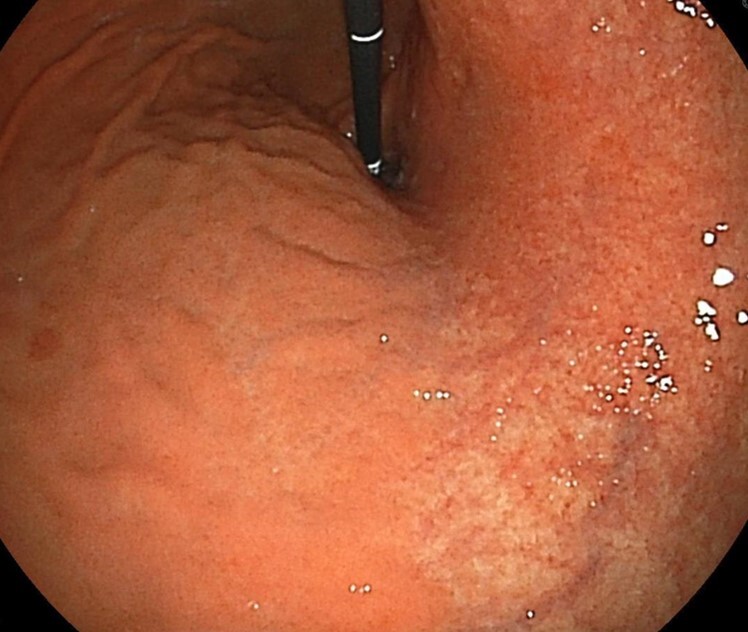

ピロリ菌陽性胃炎、粘膜の全体的な発赤や萎縮により血管が観察される

ピロリ陽性胃炎、同様に発赤と粘膜付着が強い